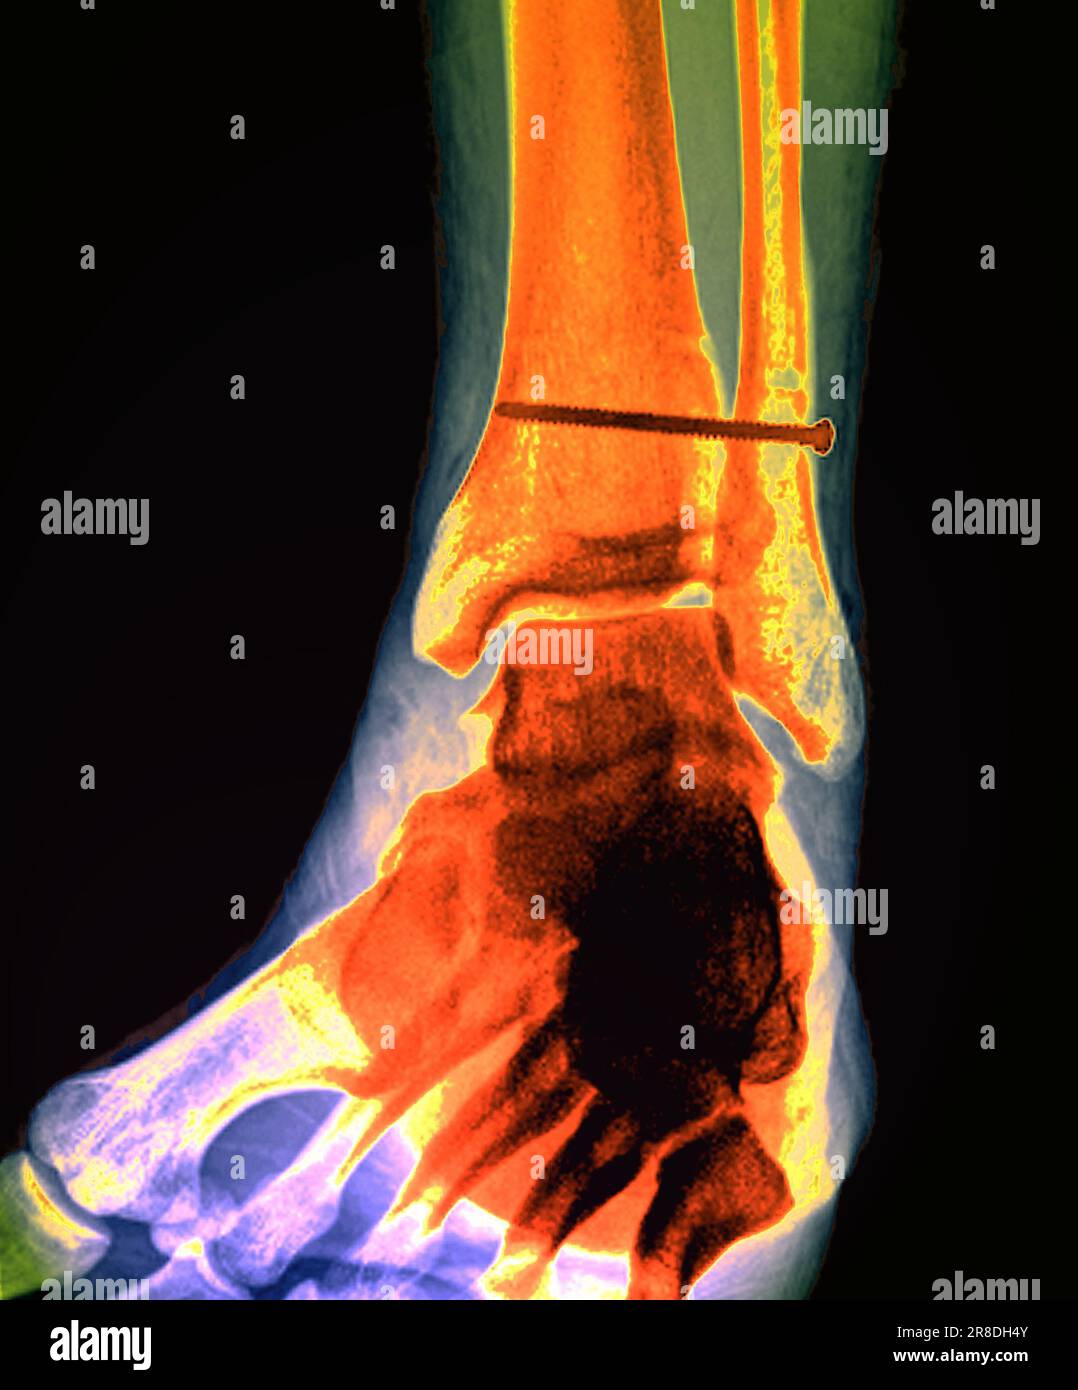

From www.alamy.com

Xray of the pinned ankle of a 32 year old male patient. A screw is Calf In Bone Fracture What is a broken leg? The proximal tibia is the upper portion of the bone where it widens to help form the knee. Healthcare providers also call broken legs fractured legs. The fibula, or calf bone, is a small bone located on the outside of the leg. A broken leg (leg fracture) is a break or crack in one of. Calf In Bone Fracture.

Coloured Xrays of the pinned ankle of a 32 year old male patient. A Calf In Bone Fracture A broken leg is a bone fracture (broken bone) in your leg. Healthcare providers also call broken legs fractured legs. Common causes include falls, motor vehicle accidents. A fibula fracture describes a break in this bone. Fibula fractures occur around the ankle, knee, and middle of the leg. Here, health care providers typically evaluate the injury and immobilize the leg. Calf In Bone Fracture.